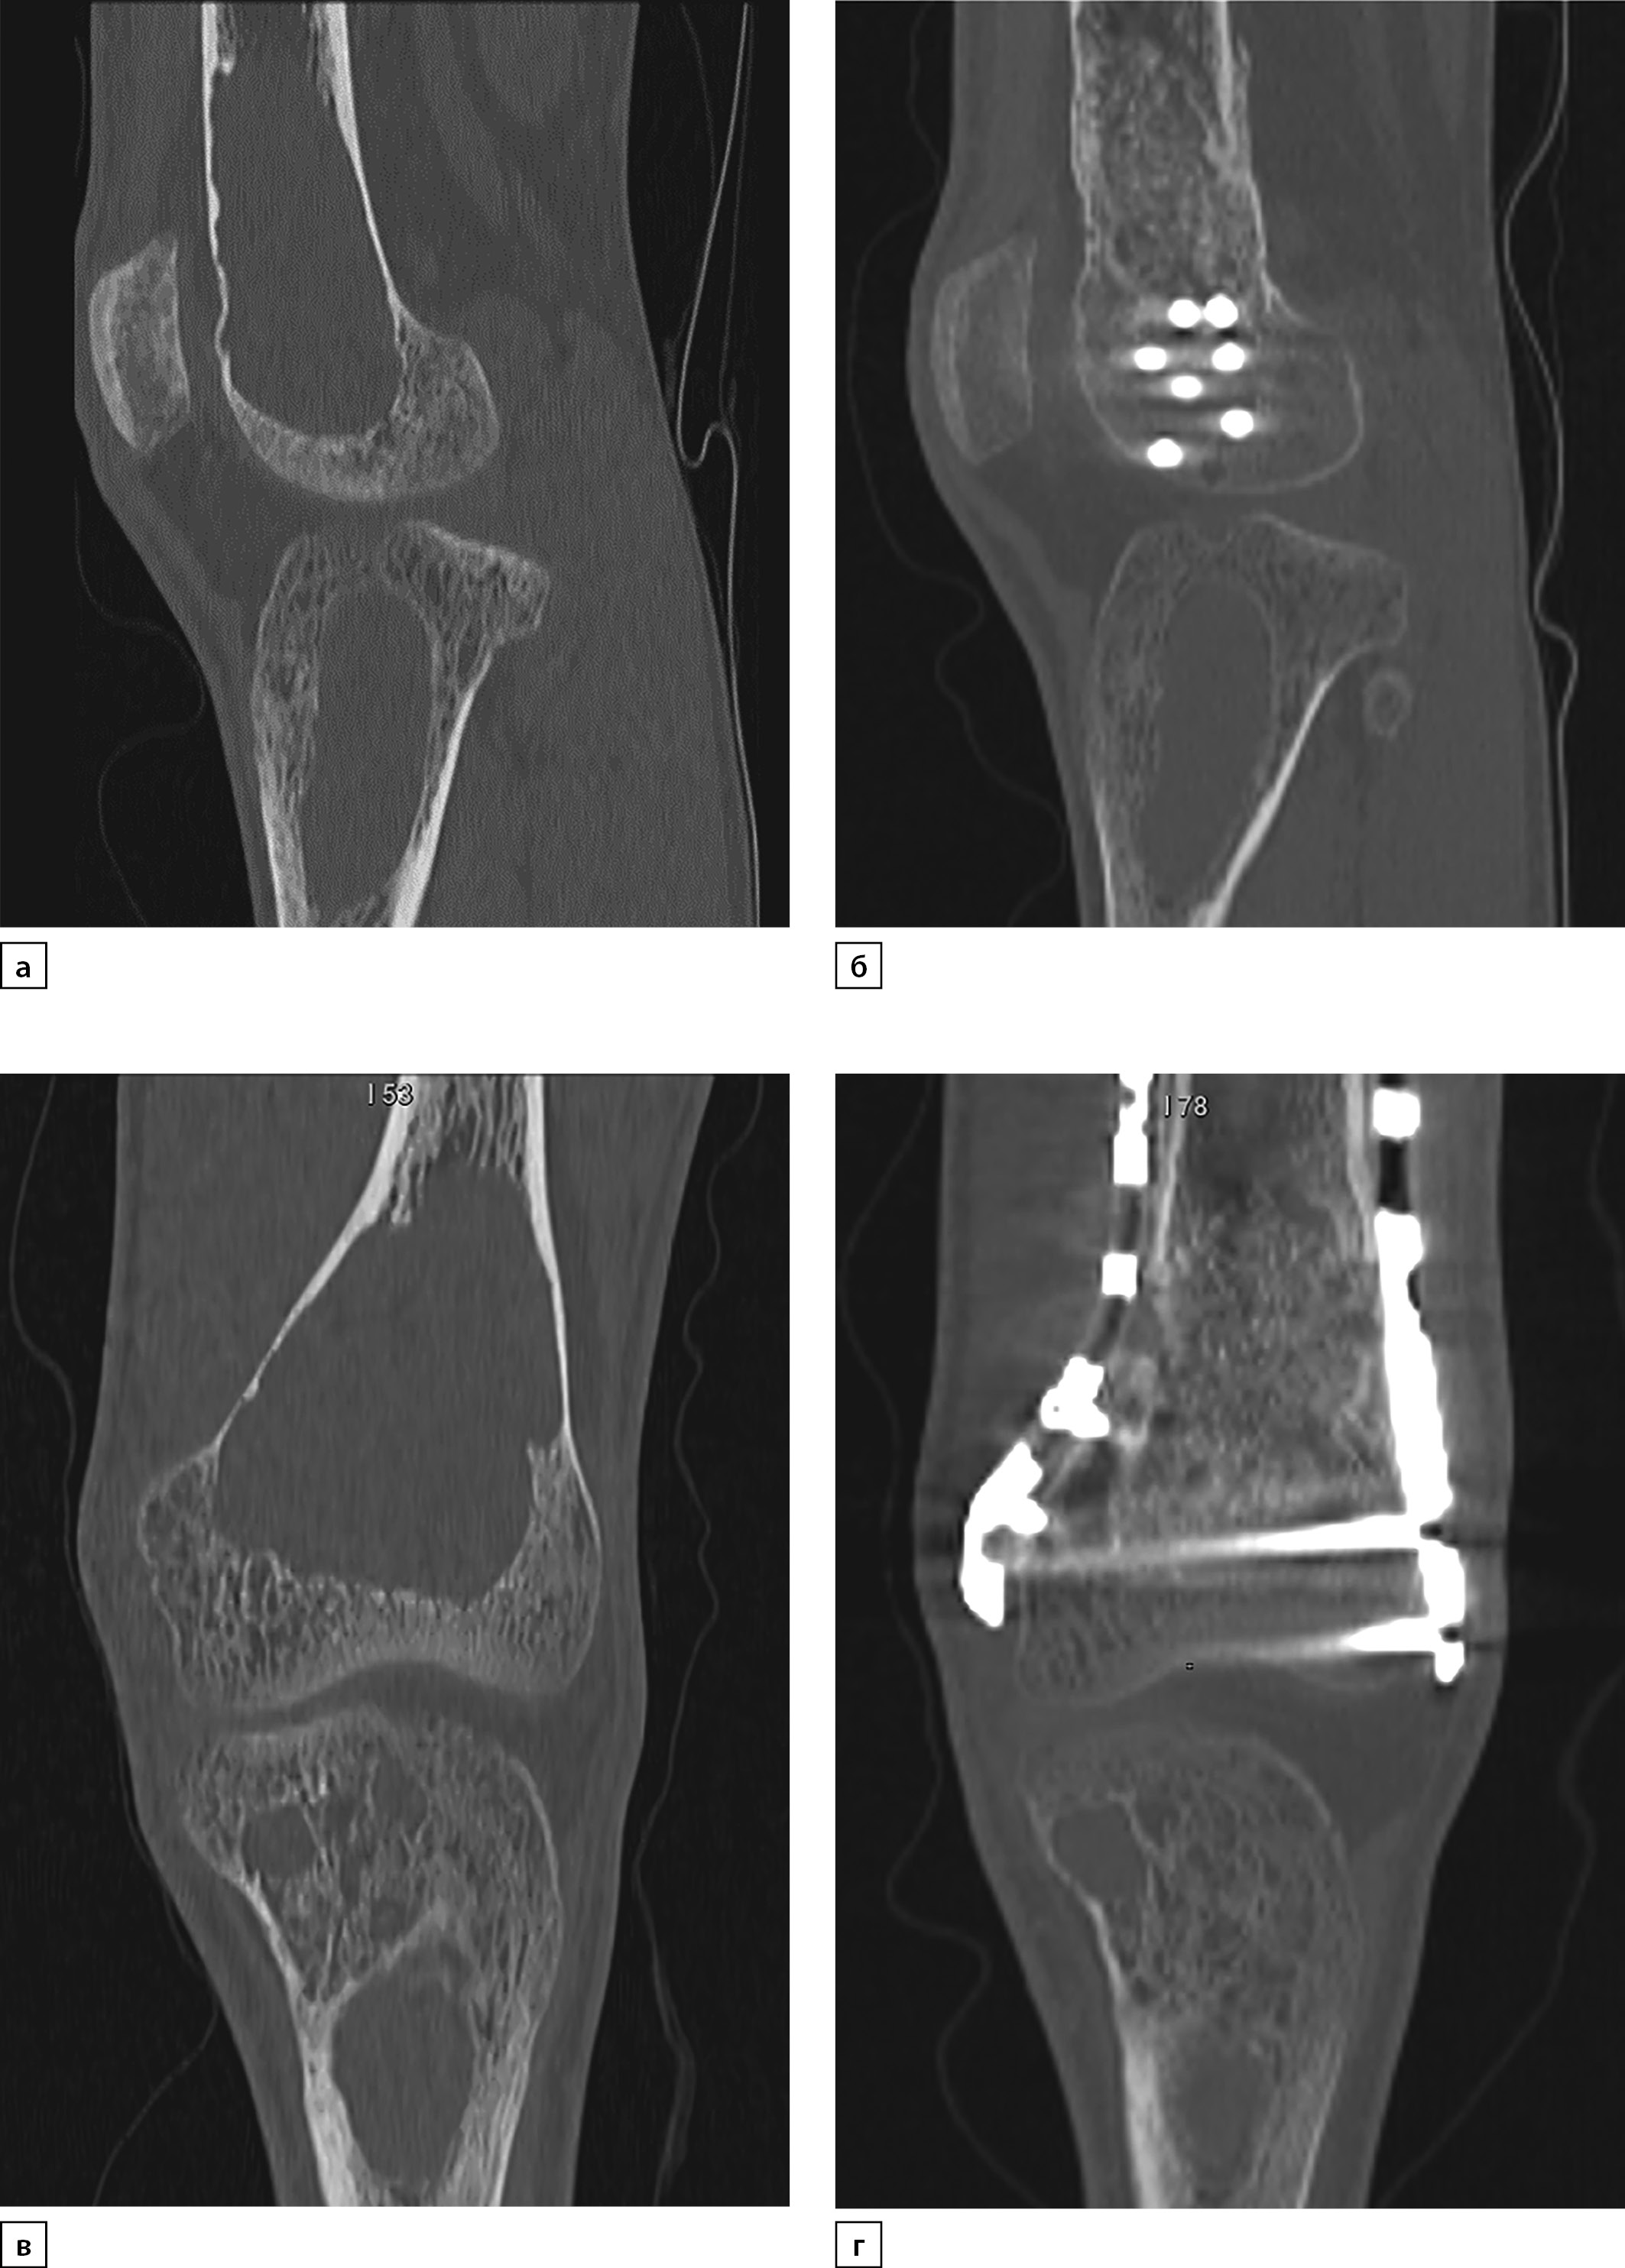

При повторной госпитализации, спустя 6 мес после хирургического лечения ПГПТ, подтверждена ремиссия заболевания (см. табл. 3). При поступлении пациент отметил хруст и выраженную боль в области левого лучезапястного сустава при подъеме тяжести. По результатам рентгенографии выявлена кистовидно-дистрофическая перестройка дистального эпиметафиза левой локтевой кости с деструкциями от 3,9 мм до 10,7 мм, клинически диагностирован перелом (рис. 6). Отмечена нормализация маркеров костного моделирования, по результатам рентгеновской остеоденситометрии — положительная динамика с приростом МПК в позвоночнике +5,7% (-0,9 SD) и в бедренной кости +7,7% (-2,4 SD), в лучевой кости — без значимых изменений +0,7% (-1,7 SD). Кроме того, при КТ нижних конечностей выявлена положительная динамика в виде преобладания участков остеосклероза в местах кистозной трансформации, признаки консолидации перелома и формирования костной мозоли левой бедренной кости (рис. 7, а, б). Учитывая низко-нормальный уровень кальция крови, а также с целью увеличения минерализации костной ткани увеличена доза альфакальцидола до 1,5 мкг/сут, продолжена терапия колекальциферолом и карбонатом кальция.

Рисунок 7. Мультиспиральная компьютерная томография левой бедренной кости в динамике: исходно (2020 г., а, в) и через 6 месяцев после паратиреоидэктомии (2021 г., б, г) в сагиттальной и корональной проекциях.